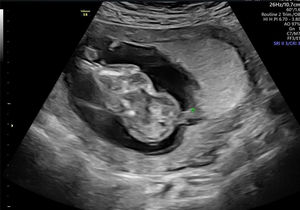

En la ecografía realizada al día siguiente en la consulta se objetivó un feto único en situación transversa izquierda con movimientos cardíacos fetales positivos. Se visualizó un encefalocele occipital de gran tamaño (fig. 1), con un defecto de la calota a nivel occipital y herniación importante de las estructuras cerebrales. En el extremo del encefalocele se objetivó una banda amniótica conectada al amnios (fig. 2). Asimismo, presentaba una ectopia cordis, con un importante defecto de la formación de la pared torácica anterior, ubicándose el corazón en el exterior de la caja torácica. En el estudio del corazón se visualizó que presentaba hipoplasia del ventrículo izquierdo. También se observó un gran defecto a nivel de la pared abdominal anterior, presentando gastrosquisis de gran cantidad de asas de intestino delgado y gran parte del hígado (fig. 3). Por último, a nivel de la columna se visualizó una cifoescoliosis severa a nivel lumbar (fig. 4). A nivel de placenta y anejos, la placenta se encontraba insertada en la cara anterior del útero con ecogenicidad acorde a la edad gestacional. En lo referente al amnios, este presentaba un fallo en la fusión con el corion (fig. 5). La cantidad de líquido amniótico era normal. No se encontraron otros hallazgos en la exploración ecográfica.